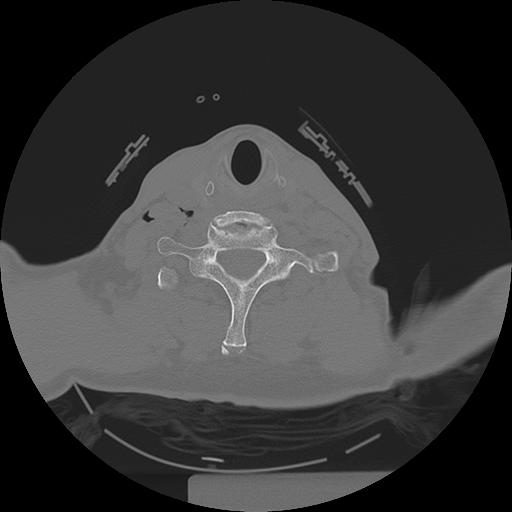

11 HUESO,,Axial,2.0,HUESO,,